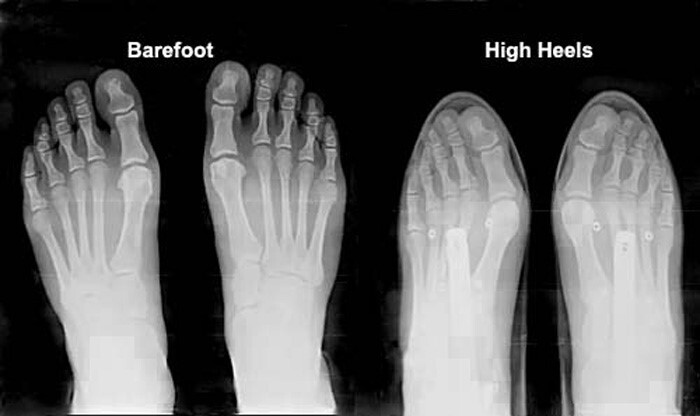

عوارض استفاده از کفش پاشنه بلند

بسیاری از بانوان علاقه دارند که از کفش چرم زنانه با پاشنه بلند استفاده کنند. اما باید بدانند که کفشهای پاشنه بلند عوارض جبرانناپذیری برای بدن به دنبال خواهند داشت و باعث ایجاد اختلال تعادل در هنگام راه رفتن میشوند و در نتیجه احتمال آسیب و زمین خوردن فرد در هنگام راه رفتن با کفش پاشنه بلند نیز افزایش پیدا خواهد کرد. در کفشهای پاشنه بلند قسمت جلوی پا پایینتر از پاشنه قرار دارد و تاندون آشیل که در خلف پاشنه واقع شده است کوتاهتر میشود. در نهایت هنگام راه رفتن این تاندون به خوبی عمل نمیکند و به مرور علاوه بر اینکه باعث درد پشت پاشنه و مچ پا میشود تعادل را هم در هنگام راه رفتن از بین خواهد برد.

نه تنها پاشنه و آشیل بلکه ستون فقرات، کمر و حتی لگن هم در اثر استفاده از کفش پاشنه بلند تحت فشار و درد قرار میگیرند؛ پس بهتر است که حتی الامکان از این مدل کفشها استفاده نکنید.